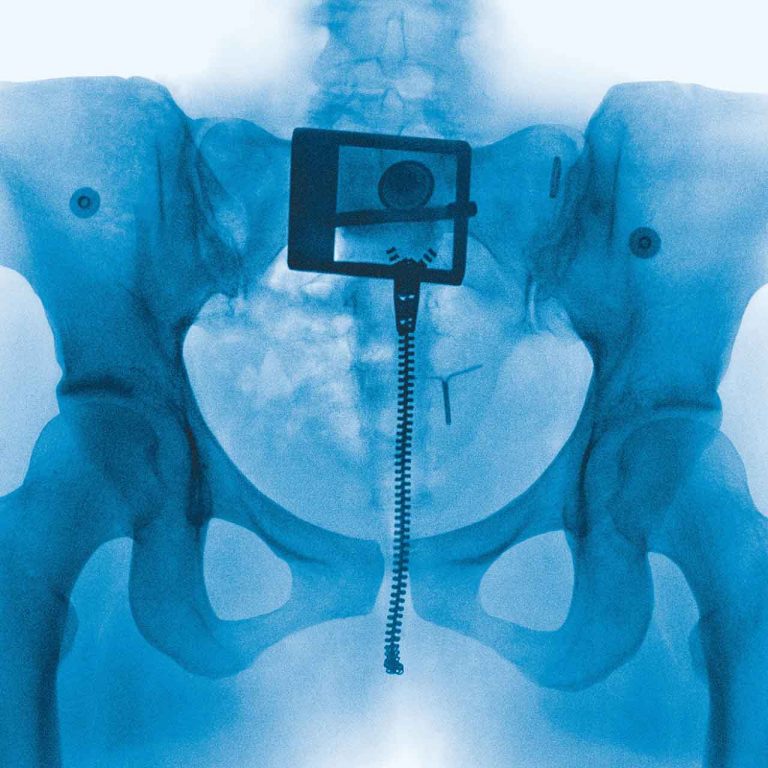

Despite concerns about his health, Ozzy Osbourne has insisted he will perform this July with Black Sabbath at his final gig. READ MORE: Sharon Osbourne and...